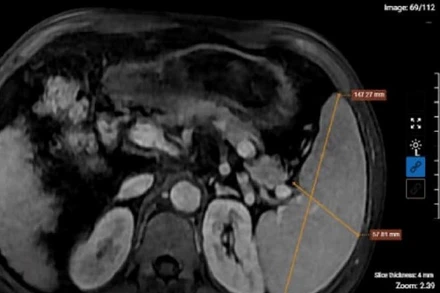

Khối u gan khổng lồ chiếm 70% diện tích gan

Các bác sĩ Trung tâm phẫu thuật Gan mật, Tiêu hóa, Bệnh viện Bệnh Nhiệt đới Trung ương vừa phẫu thuật thành công một ca ung thư gan giai đoạn muộn, có khối u kích thước rất lớn, xâm lấn tĩnh mạch cửa, biến chứng nguy hiểm đe dọa tính mạng.